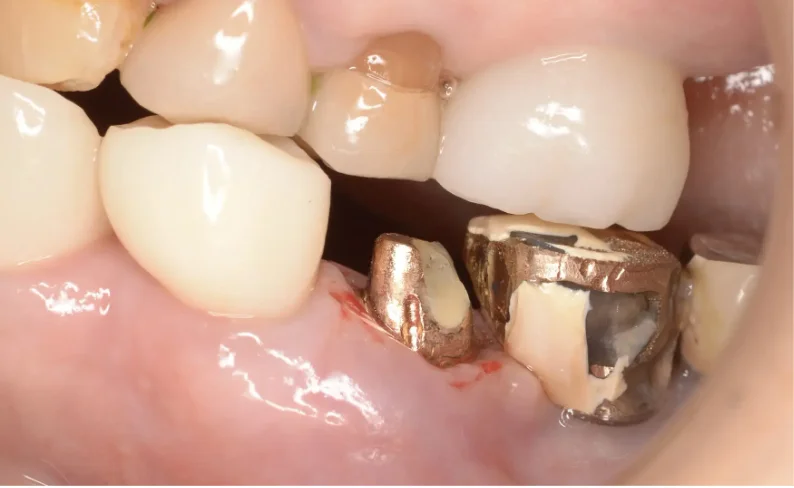

Before

After

インプラント周囲炎に対応(80代女性)

2ヶ月 / 総額40,000円リスク・副作用:インプラント周囲炎はご自分の歯の歯周病と同じで、一度落ち着いてもケアを怠ると再発してしまいます。 いい状態を維持できるように、しっかりメンテナンスが必要です。